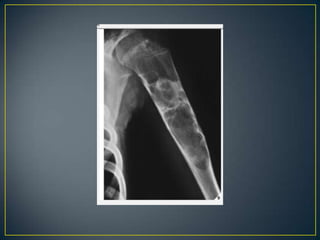

• Identification of tumor bone within or adjacent to the area

of destruction should alert the radiologist to the possibility

of osteosarcoma/reactive sclerosis.

• Osteosarcoma-cloudy - cotton like fluffy deposits.